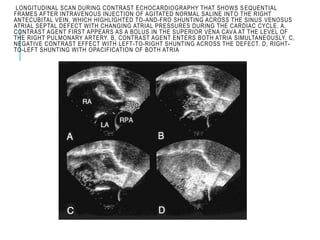

LONGITUDINAL SCAN DURING CONTRAST ECHOCARDIOGRAPHY THAT SHOWS SEQUENTIAL

FRAMES AFTER INTRAVENOUS INJECTION OF AGITATED NORMAL SALINE INTO THE RIGHT

ANTECUBITAL VEIN, WHICH HIGHLIGHTED TO-AND-FRO SHUNTING ACROSS THE SINUS VENOSUS

ATRIAL SEPTAL DEFECT WITH CHANGING ATRIAL PRESSURES DURING THE CARDIAC CYCLE. A,

CONTRAST AGENT FIRST APPEARS AS A BOLUS IN THE SUPERIOR VENA CAVA AT THE LEVEL OF

THE RIGHT PULMONARY ARTERY. B, CONTRAST AGENT ENTERS BOTH ATRIA SIMULTANEOUSLY. C,

NEGATIVE CONTRAST EFFECT WITH LEFT-TO-RIGHT SHUNTING ACROSS THE DEFECT. D, RIGHT-

TO-LEFT SHUNTING WITH OPACIFICATION OF BOTH ATRIA

Longitudinal scan ofthe atrial septum, which highlights sinus venosus atrial septal defect (arrowhead) located in the superior fatty limbus of the atrial septum (AS). The defect lies immediately inferior to the right pulmonary artery (RPA), viewed in its short axis, and to the orifice of the superior vena cava (SVC), viewed in its long axis. The SVC overrides the left and right atria (LA, RA). The fossa ovalis (FO) portion of the atrial septum is intact. Note the pathognomonic feature, ie, the absence of atrial septal

LONGITUDINAL SCAN DURINGCONTRAST ECHOCARDIOGRAPHY THAT SHOWS SEQUENTIAL FRAMES AFTER INTRAVENOUS INJECTION OF AGITATED NORMAL SALINE INTO THE RIGHT ANTECUBITAL VEIN, WHICH HIGHLIGHTED TO-AND-FRO SHUNTING ACROSS THE SINUS VENOSUS ATRIAL SEPTAL DEFECT WITH CHANGING ATRIAL PRESSURES DURING THE CARDIAC CYCLE. A, CONTRAST AGENT FIRST APPEARS AS A BOLUS IN THE SUPERIOR VENA CAVA AT THE LEVEL OF THE RIGHT PULMONARY ARTERY. B, CONTRAST AGENT ENTERS BOTH ATRIA SIMULTANEOUSLY. C, NEGATIVE CONTRAST EFFECT WITH LEFT-TO-RIGHT SHUNTING ACROSS THE DEFECT. D, RIGHT- TO-LEFT SHUNTING WITH OPACIFICATION OF BOTH ATRIA